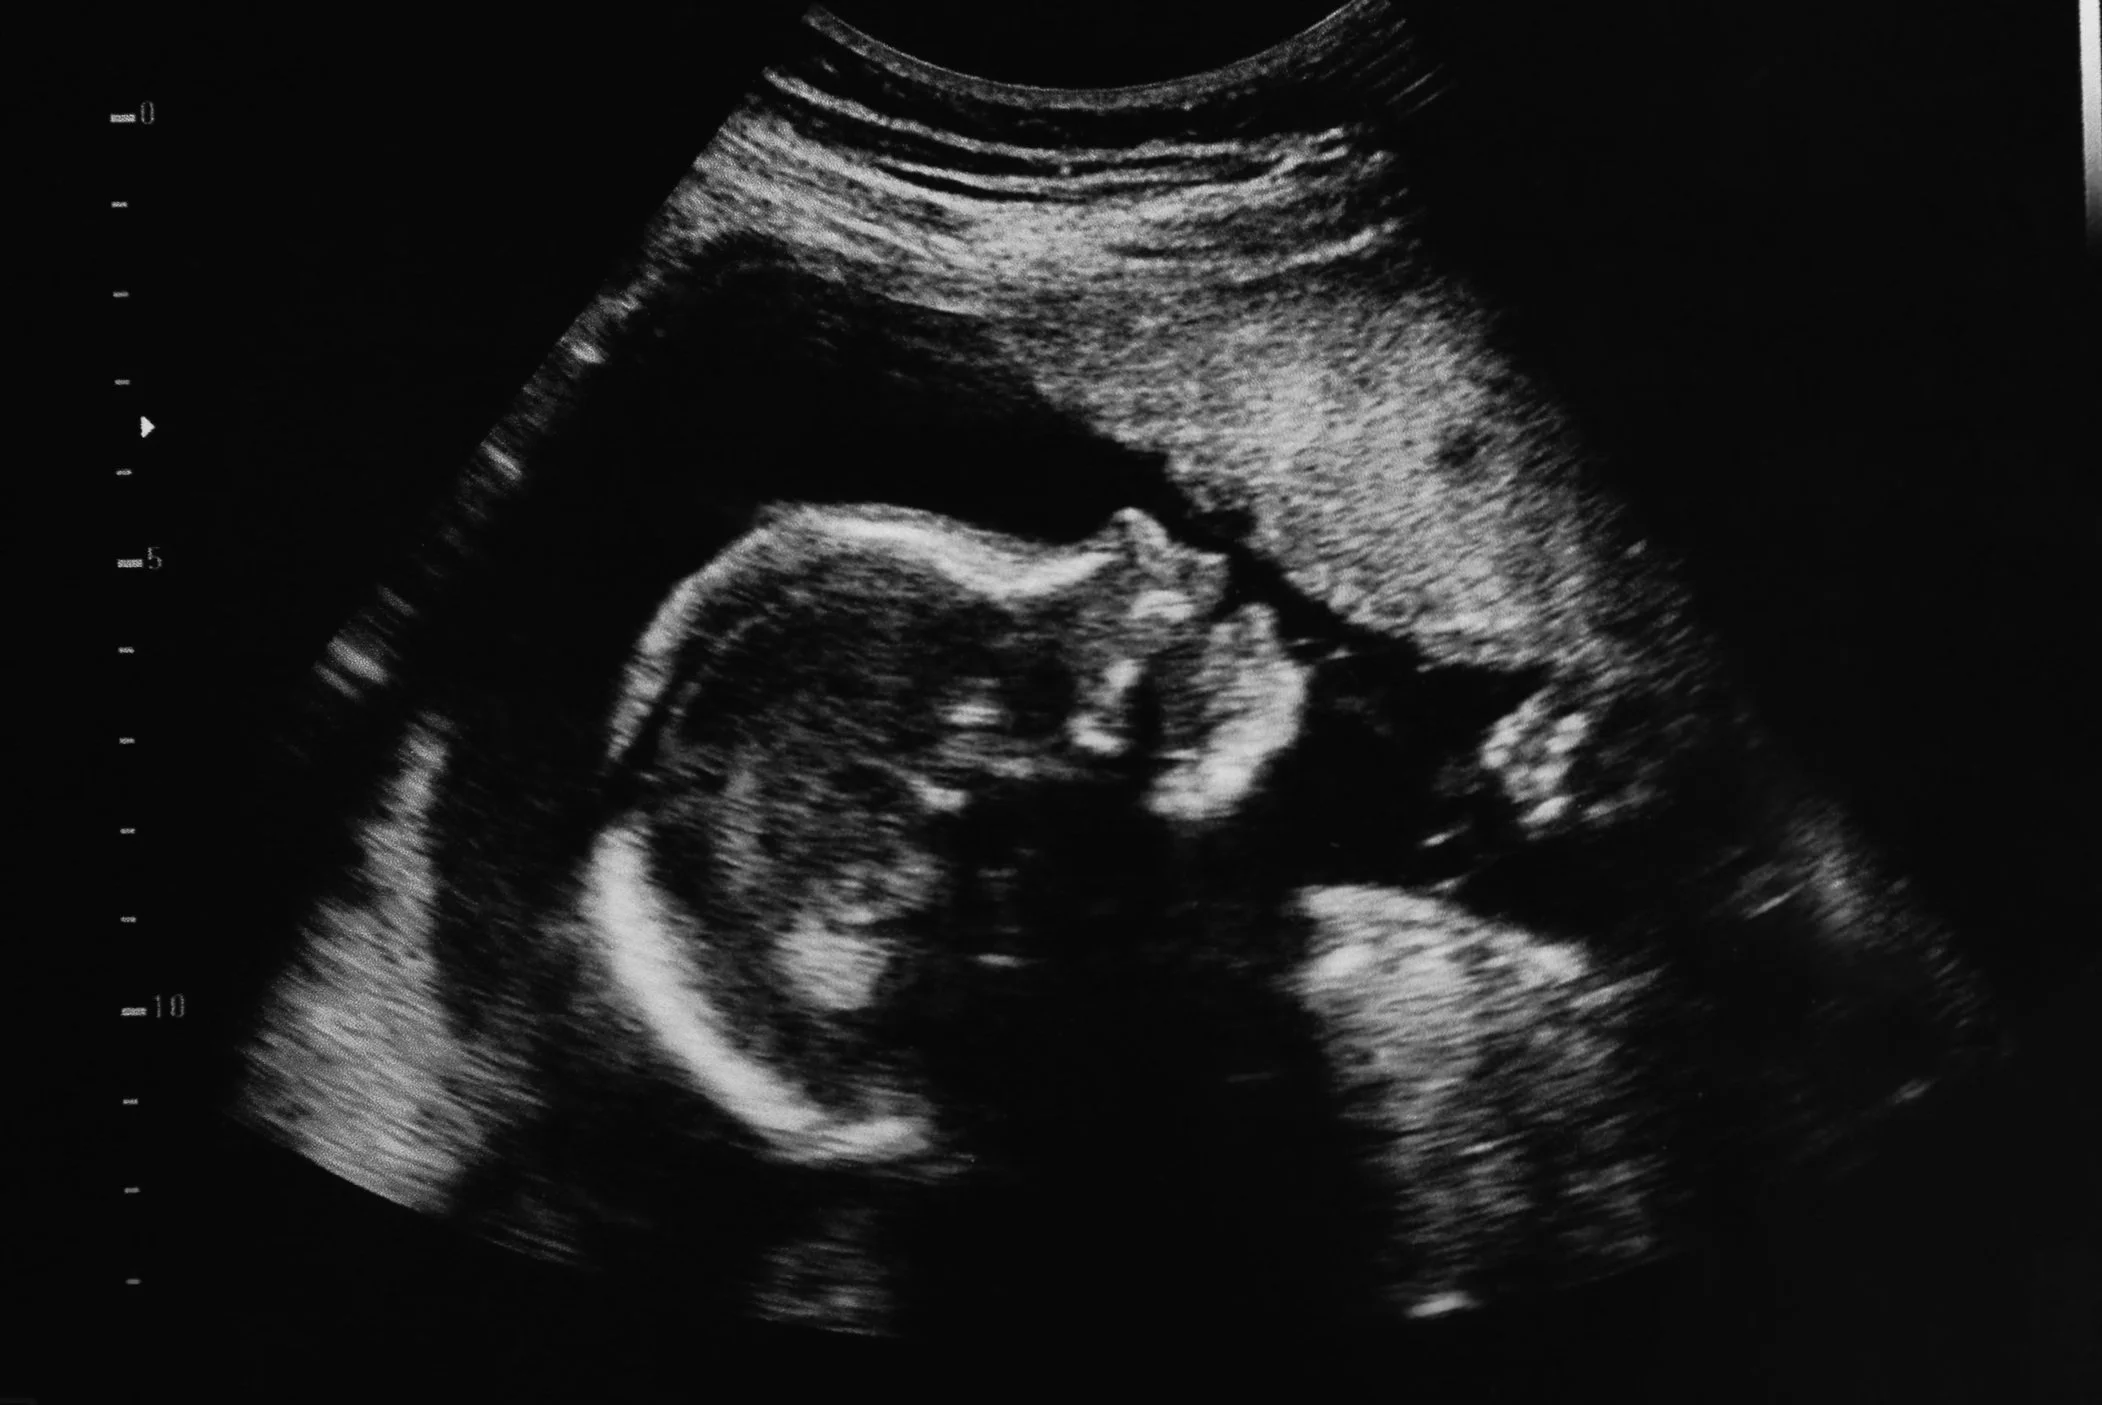

Black and white ultrasound image of a developing fetus inside the womb.

• Obstetric Ultrasound – monitors pregnancy, fetal growth, and development.

• 3D/4D Ultrasound – often used in obstetrics for detailed fetal imaging.

Pregnancy Ultrasound Packages

For those expecting, Evolution Imaging offers special Pregnancy Ultrasound Packages designed to enhance your prenatal experience. Choose from our tailored options for an intimate first look at your new arrival: